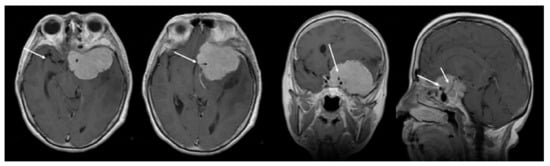

3.2. Preoperative Clinical and Radiological Data

| Preoperative Clinical Data | Preoperative Radiological Evaluation | ||||

|---|---|---|---|---|---|

| Clinical Signs | n (%) | MRI Characteristics | n (%) | ||

| cognitive decline | mild | 6 (46%) | sphenoidal ridge tumor origin | medial | 9 (43%) |

| medium | 5 (38.5%) | middle and medial | 6 (28.5%) | ||

| severe | 2 (15.5%) | lateral | 6 (28.5%) | ||

| visual disfunctions | visual field | 6 (54.5) | cavernous sinus invasion | 5 (24%) | |

| visual acuity | 5 (45.5) | optic canal invasion | 6 (28.5%) | ||

| headaches | 9 (43%) | major arterial encasement | total | 11 (52%) | |

| aphasia | 6 (28.5) | partial | 10 (48%) | ||

| motor deficits | 6 (28.5) | cerebral edema | 21 (100%) | ||

| oculomotor nerve palsy | 3 (14%) | average diameter | 6.3 cm ranging between 5–7.4 cm | ||

| seizures | 2 (9.5%) | ||||